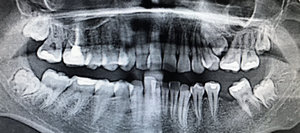

Может ли спустя полгода пломба дать о себе знать таким образом? Как действовать? Рентген прилагаю.

На Вашем снимке, конечно, ничего не видно, но теоретически может. Изоляция пульпы не выдерживает герметизацию, и зуб необходимо, скорее всего, депульпировать.

Также можно попробовать сменить пломбу, лучше изолировать камеру и понаблюдать.